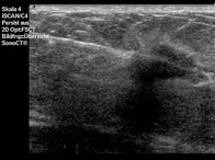

Die Stanzbiopsie erfolgt unter Ultraschallsicht. Nach Desinfektion werden die Haut und der Weg zum auffälligen Befund mit einer feinen Nadel betäubt. Anschließend wird über einen kleinen Hautschnitt eine Punktionsnadel eingeführt und bis an den Befund herangebracht. Durch Auslösen eines Federmechanismus durchsticht die Punktionsnadel den Herdbefund und schneidet dabei ein kleines Gewebestück heraus. Üblicherweise werden zwischen 3 bis 5 Gewebestücke aus unterschiedlichen Arealen eines Herdbefundes entnommen. Die gewonnenen Gewebeproben werden anschließend zur histologischen Begutachtung in die Pathologie übersandt. Die Stanzbiopsie eines Befundes nimmt etwa 20 bis 30 Minuten in Anspruch. Komplikationen, wie Blutergüsse oder eine Entzündung sind insgesamt selten und gut therapierbar.